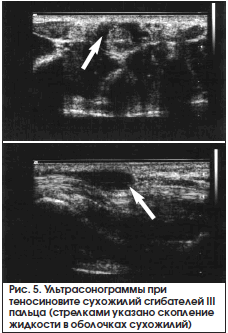

При ультразвуковом исследовании можно обнаружить изменение синовиальных оболочек и жидкостный компонент (рис. 5).